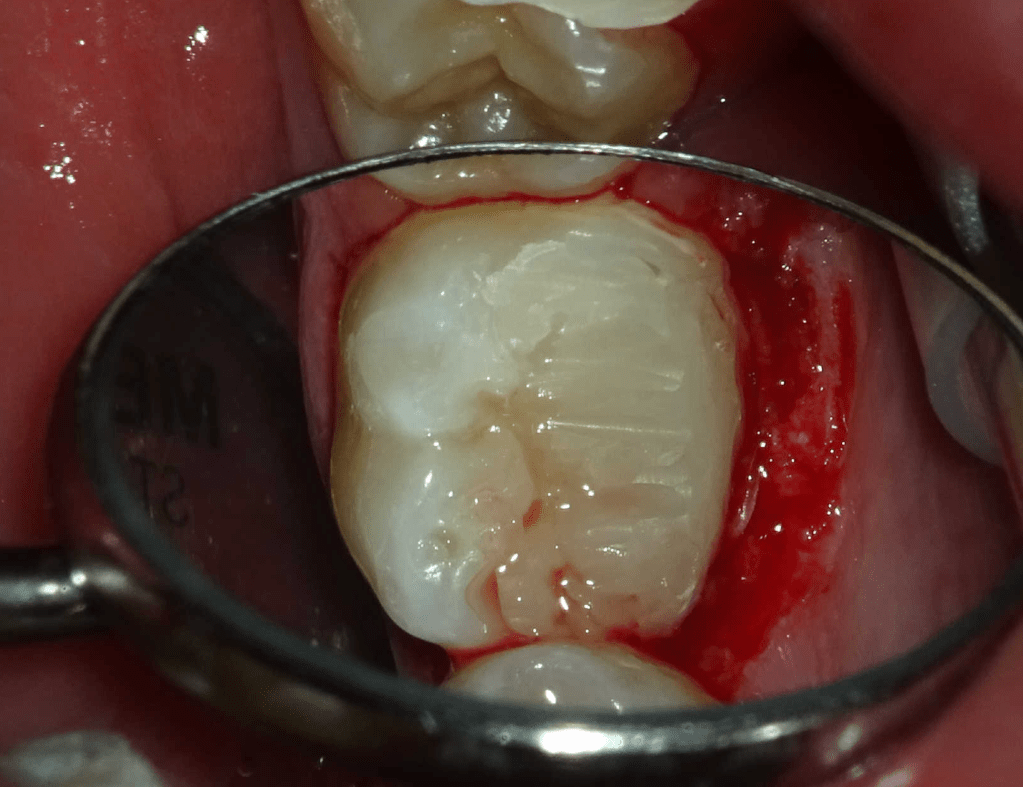

Reco preendo, 2o Molar superior